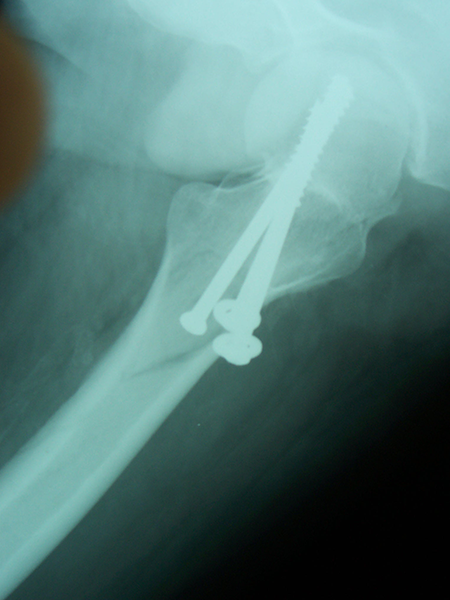

Case:9 Comminuted Intertrochanteric Fracture

Patient aged 75 years with Comminuted Intertrochanteric fracture treated with closed reduction & Ender’s nailing.

Pre-op Ap

Pre-op Lateral

Post-op Ap

Post-op Lateral